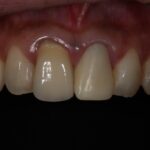

ダイレクトボンディングなどの

審美治療も高精度に対応

肉眼では見えない細かな部分まで拡大して確認できるため、削りすぎを防ぎ、再発リスクを抑えた質の高い治療が可能です。